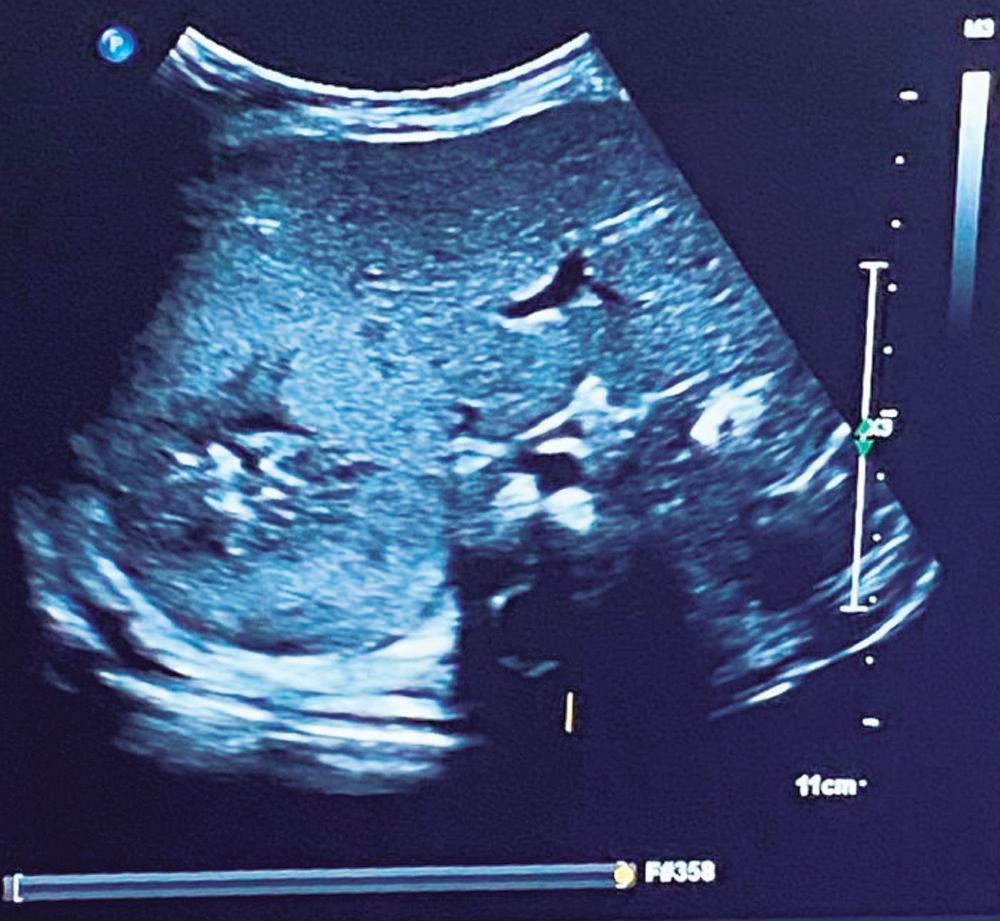

Hemangioendotelioma hepático infantil con elevación de alfa-fetoproteína: reporte de caso y revisión

María Laura Valberdi Lecce, María Cristina Arregui, Carmen Lucía Otegui Banno, Andrea Besga